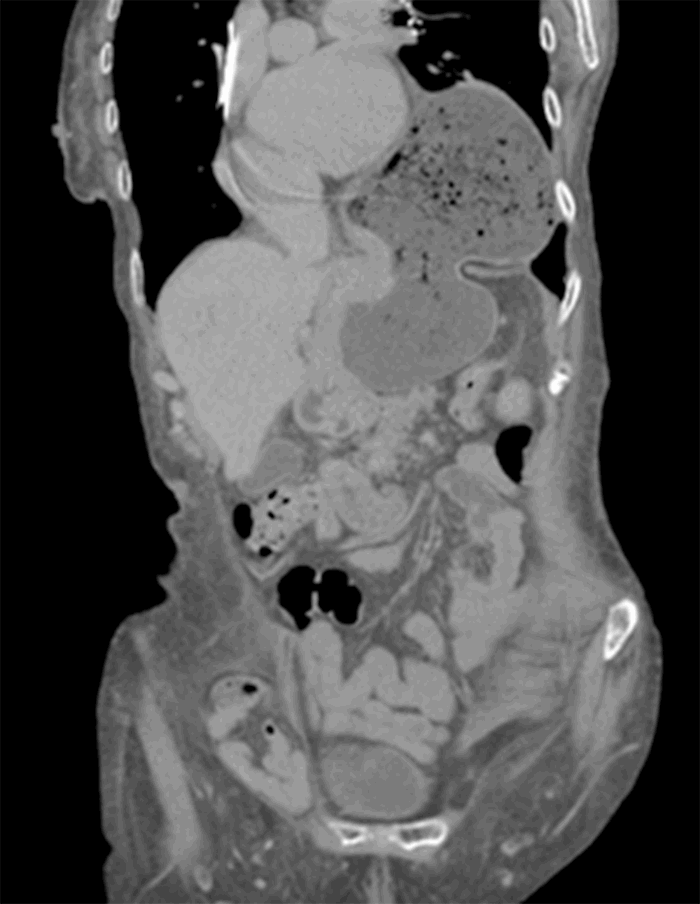

Computed tomography (CT) from outside facility performed earlier in the week revealed gastric outlet obstruction (GOO) caused by a massive type III PEH (Figure 1–4). She was subsequently discharged from this facility as she did not want surgical intervention and opted for hospice care. She presented to the ED later that week for persistent pain. At this time, it was decided to obtain a barium swallow instead of the repeat CT, demonstrating an intrathoracic stomach with concern for underlying gastric volvulus (Figure 5). Due to worsening obstructive symptoms, pain, and evidence of gastric outlet obstruction with possible gastric volvulus, it was recommended she undergo surgical intervention that day.

Figure 1. CT coronal view demonstrating large intrathoracic PEH.

Figure 2. CT coronal view demonstrating large intrathoracic PEH.